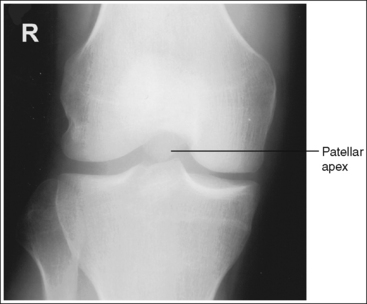

The knee demonstrates an AP projection. The medial and lateral femoral epicondyles are in profile, the femoral condyles are symmetrical, the intercondylar eminence is centered within the intercondylar fossa, and the tibia is superimposed over 0.25 inch (0.6 cm) of the fibular head.

• To obtain an AP knee projection, place the patient in a supine position with the knee fully extended. Internally rotate the leg until an imaginary line drawn between the medial and lateral femoral epicondyles is positioned parallel with the IR (Figure 6-71). This positioning places the medial and lateral femoral epicondyles at equal distances from the IR as well as medially and laterally in profile, respectively. It also centers the intercondylar eminence within the intercondylar fossa and draws the fibular neck and a portion of the fibular head from beneath the tibia.

• Effect of rotation. If the femoral epicondyles are not positioned parallel with the IR, an AP projection has not been obtained. If the patient's leg was not internally rotated enough to place the epicondyles at equal distances from the IR, they are not in profile, the medial femoral condyle appears larger than the lateral condyle, and the tibia is superimposed over more than 0.25 inch (0.6 cm) of the fibular head (see Image 54). If the patient's leg was internally rotated more than needed to place the femoral epicondyles at equal distances from the IR, the epicondyles are not demonstrated in profile, the lateral femoral condyle appears larger than the medial condyle, and the tibia is superimposed over less than 0.25 inch (0.6 cm) of the fibular head (see Image 55).

• Center the central ray to the midline of the knee at a level 1 inch (2.5 cm) distal to the palpable medial epicondyle to place the knee joint in the center of the exposure field. (As long as the knee remains extended, an alternative central ray placement is 0.5 inch (1.25 cm) distal to the patellar apex.) Open the longitudinal collimation enough to include one fourth of the distal femur and proximal lower leg. Transverse collimation should be to within 0.5 inch (1.25 cm) of the knee skin line.

The femoral epicondyles are not in profile, the medial femoral condyle appears larger than the lateral condyle, and the fibular head demonstrates more than 0.25 inch (0.6 cm) of tibial superimposition. The leg was externally rotated.

Internally rotate the leg until the femoral epicondyles are at equal distances from the IR.

The femoral epicondyles are not in profile, the lateral femoral condyle appears larger than the medial condyle, and the fibular head demonstrates less than 0.25 inch (0.6 cm) of tibial superimposition. The leg was internally rotated.

Externally rotate the leg until the femoral epicondyles are at equal distances from the film.